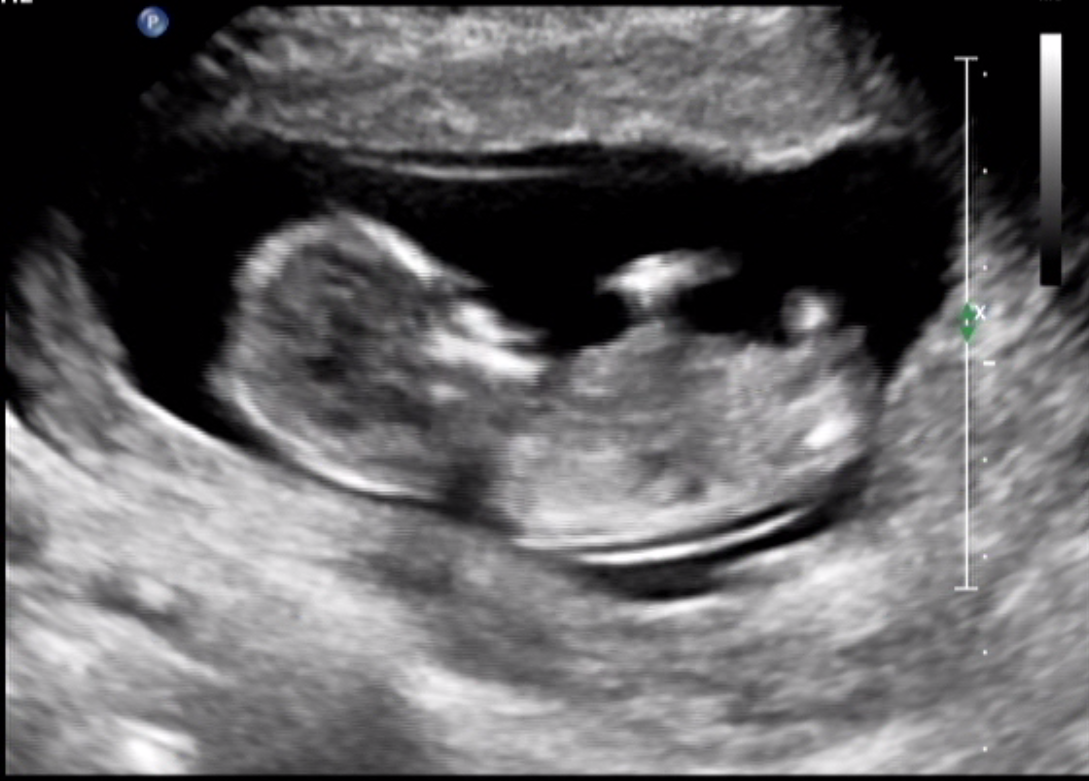

Hello! baby is 13+2 weeks. would love your thoughts

Thinking girl

girly

Girl lean